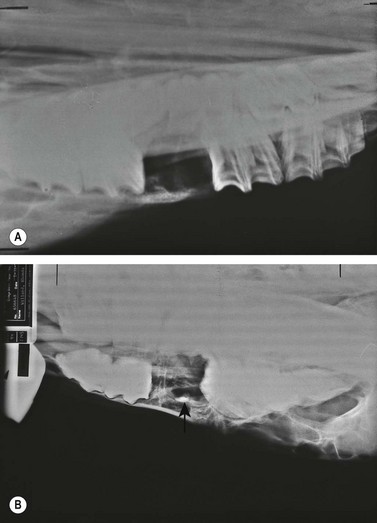

Because the tooth is usually fragmented while being repulsed, it should be examined to determine if pieces are missing, and the alveolus should be inspected visually and digitally for osseous and dental fragments. Dental fragments still attached to the alveolus may be difficult to detect. The tooth of a young horse is more brittle than that of an old horse, and therefore, is more likely to be fragmented. After the alveolus is curetted, irrigated, suctioned, and dried, it should be examined radiographically to detect osseous or dental fragments that may remain within it. A ventrodorsal radiographic projection of the alveolus, obtained with the cassette in a sterile sleeve, provides a good view of the vacated alveolus (Fig. 20.49). Pulling the mandible laterally may allow a view of the entire vacated alveolus unobstructed by superimposition of teeth in the opposing arcade.

image

Fig. 20.49 (A) A ventrodorsal radiographic projection of the alveolus provides a good view of the alveolus. Pulling the mandible laterally may allow a view of the entire vacated alveolus unobstructed by superimposition of teeth in the opposing arcade. (B) A dorsoventral radiographic projection showing a dental fragment within an alveolus (arrow points to fragment).